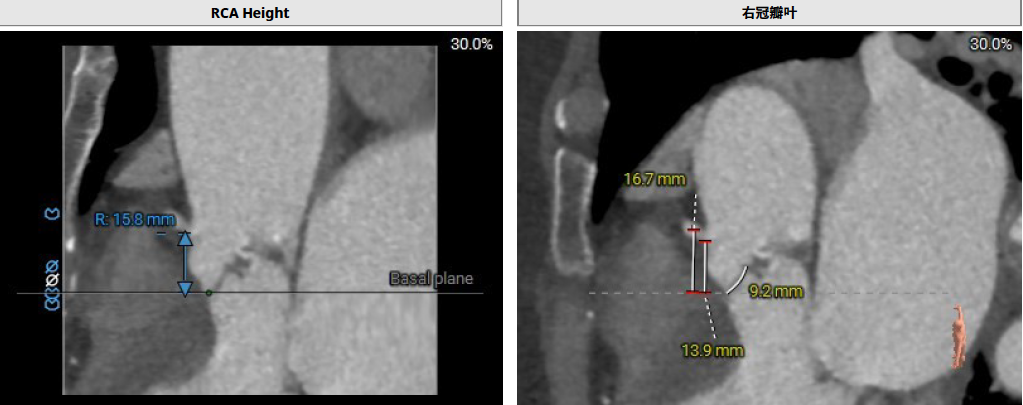

患者Type1 二叶瓣,右无融合,融合嵴钙化,钙化主要分布瓣叶缘和融合嵴处,无冠窦底钙化向下延伸至流出道4mm处。Annulus面积398mm²,LVOT面积400mm²,SOV 27.6-30.9mm,STJ高度21.3mm,内径29-32.7mm,瓣环角度62°,升主动脉扩张,左冠高度14.9mm,左冠瓣叶长度15.7mm,右冠高度15.8mm,右冠瓣叶长度9.2mm,模拟植入21#瓣膜VTC LCA 2.4mm,右侧髂内分叉处可见钙化,右侧髂外动脉最细为6.1mm,左侧髂外动脉最细为6.1mm,外周入路尚可。

左冠高度14.9mm,左冠瓣叶长度15.7mm,右冠高度15.8mm,右冠瓣叶长度9.2mm,模拟植入21#瓣膜VTC LCA 2.4mm

使用Supra annulus画圆法评估21# RENATUS瓣膜植入情况: